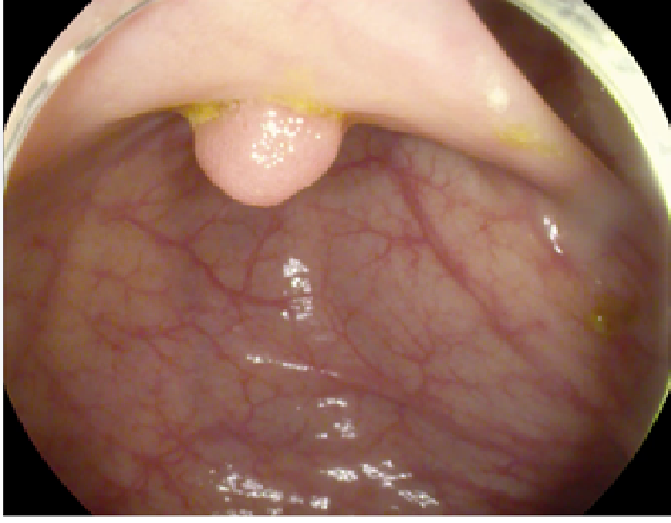

4.1 Dataset Specifications and Augmentation

The study used a publicly available dataset of polyp-frames obtained from the ETIS-Larib database [34], containing 196 polyp images. These images were obtained from 34 different colonoscopy videos of 44 different polyps with various appearances and sizes, having a resolution of 1225×96612259661225\times 966 pixels. The ground truth of polyp areas for polyp datasets is determined by expert video endoscopists. A CNN model trained with such a small amount of data is likely to be meaningless and unstable, so data augmentation was performed on the polyp dataset. Data augmentation had to be performed on the colonoscopy images by considering vivid variations. Otherwise over-fitting would have occurred. In a colonoscopy imagery, polyps exhibits large variations in location, color, and scale. Moreover, variations in brightness and definition also occur due varrying the view-point of the camera. Therefore, in addition to photometric distortions and geometric distortions, we also have considered zooming, shearing, and altering brightness as strategies for data augmentation.

For photometric distortions, we controlled brightness and contrast as an enhancement, while blurring by adding noise with a standard deviation (σ)𝜎(\sigma) of 1.0. Similarly, for geometric distortions, clock-wise rotation of the polyp images with angles of 90°90°, 180°180°, and 270°270° were performed. Zoom-in and zoom-out with zooming parameters such as 30.00% and 10.00% were performed to obtain different scales of polyp images. Lastly, shearing for both the x-axis and the y-axis was performed to shear the images from left to right and top to bottom, respectively. Fig. 4 shows photometric and geometric forms of image augmentation. In this way, we augmented the data set of the ETIS-Larib database from 196 polyp images to 2,156 images, which is more suitable for training the proposed deep CNN model.